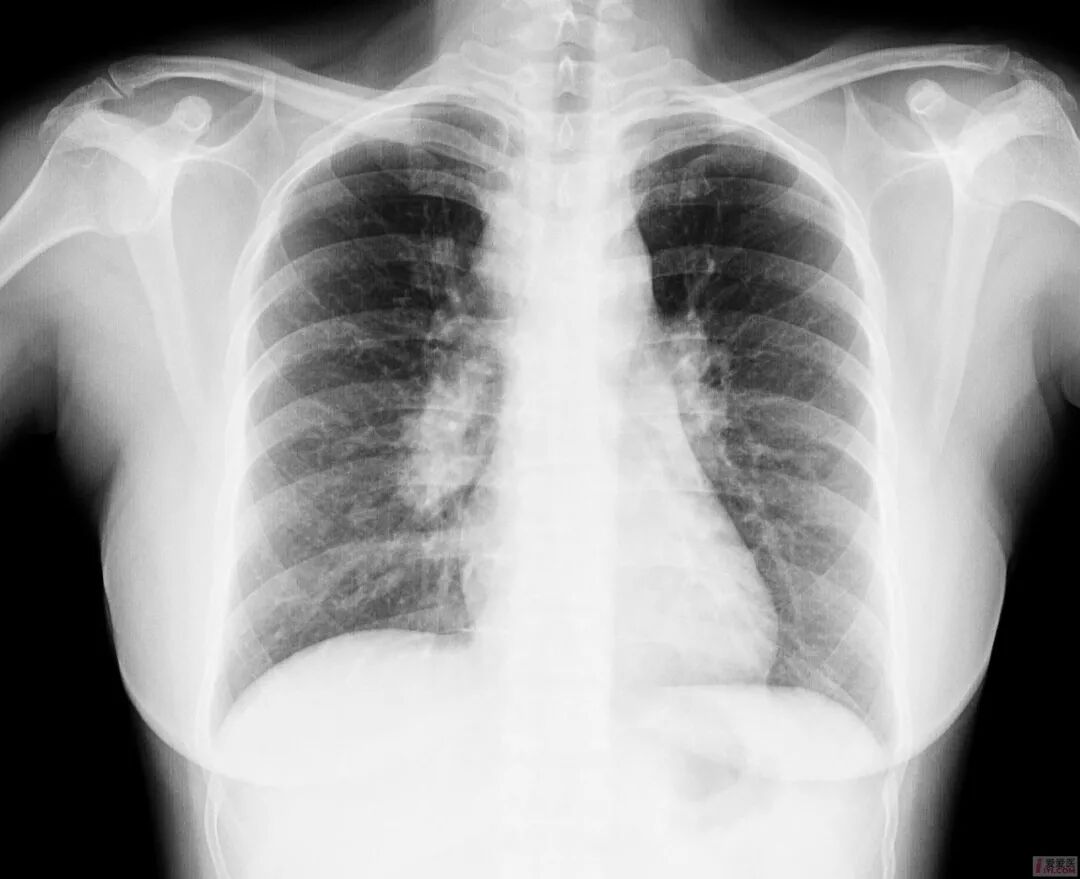

胸透和胸片主要用于检查诊断肺部疾病、心脏的大小、肋骨、胸膜、胸壁纵隔、支气管。为减少X线的损害,患者做检查不宜过多。

胸片DR和胸透还是有很大的区别的,当然它们都是检查胸部,也就是看肺这一块的。但是它们的区别还是比较大的,首先第一点它的辐射剂量有很大的差别,胸片DR,它的辐射剂量是非常的小,而胸透相对来说就要大一些了,主要是跟它辐射的时间有关系。

做胸片DR检查的话,它辐射的时间是非常短的,一般也就是零点零几秒的时间,非常的短,而胸透检查它这个辐射时间相对来说就要长一些了,一般是需要十秒钟的时间。当然如果发现有可疑的病灶,可能需要看的时间要更长一些了。正因为是这样,所以现在很多医院已经基本上取消了胸透检查了,都是用胸片来进行替代。

胸片的话一般是可以照出一张片子来,而胸透只是医生通过目视,通过眼睛来看,看完之后得出一个纸质报告,是没有这种片子的。

最常用X光片、CT大致了解选X光片,细致分析选CT肺的检查一般不选核磁

胸部